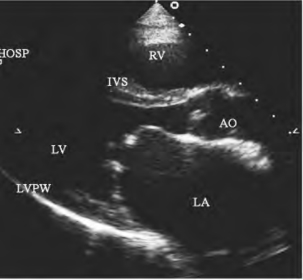

1.17.1第一节 二尖瓣疾病

1.17.1.1一、二尖瓣狭窄